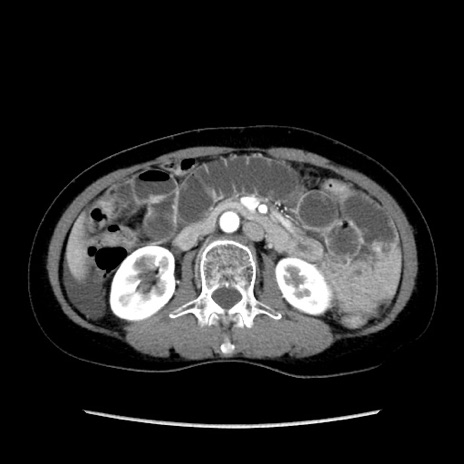

症例32(横断像)

【症例】40歳代 女性

【主訴】上腹部痛、嘔気・嘔吐

【現病歴】約9時間前頃から急に上腹部痛、嘔気、嘔吐が出現。改善しないため救急要請。

【既往歴】子宮頚癌(広汎子宮全摘術、放射線療法)、腸閉塞

【身体所見】腹部:平坦、軟、腸雑音亢進、上腹部を中心に腹部全体に圧痛あり。

【データ】WBC 8400、CRP 0.03